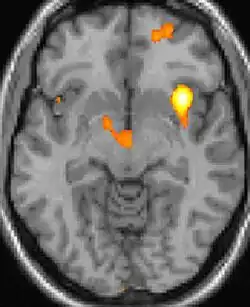

VBM mostrando diferenças estruturais entre cérebros

As reais causas da cefaleia em salvas (CES) ainda são desconhecidas, mas, de acordo com alguns estudos, os padrões das crises, as influências pelo horário do dia e as estações sugerem que o relógio biológico do corpo está envolvido. Nos seres humanos, o relógio biológico está situado no hipotálamo. Durante um ataque, o hipotálamo libera substâncias químicas que podem estimular as células nervosas no cérebro, causando dor e outros sintomas. A hiperatividade nervosa também pode causar um alargamento (vasodilatação) das artérias no lado afetado do cérebro. Uma teoria é que as dores são causadas por um alargamento dos vasos sanguíneos, que pressionam sobre os tecidos nervosos próximos, causando dor.[5] Exames de ressonância magnética sugerem dilatação da artéria oftálmica durante uma crise de cefaleia, enquanto a tomografia por emissão de pósitrons (PET) revela atividade dentro do seio cavernoso. Em alguns casos, existem fatores genéticos também, pois é mais comum entre familiares.[6]